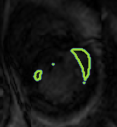

4.2 Visual assessment

We select the case that achieves the highest and lowest dice score for visual assessment. Fig. 4 shows example segmentation results where the proposed method achieved the highest agreement with the ground truth delineations. Fig. 5 shows example segmentation results where the proposed method achieved the lowest agreement with the ground truth delineations.

| (a) LV BG | (b) RV BG | (c) LV NM | (d) LV ME | (e) LV MS |